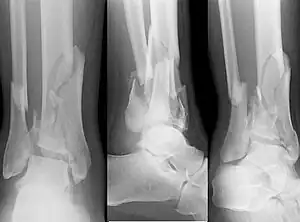

X-ray of a fracture involving the articular surface of the Tibia | |

A pilon fracture, is a fracture of the distal part of the tibia, involving its articular surface at the ankle joint. Pilon fractures are caused by rotational or axial forces, mostly as a result of falls from a height or motor vehicle accidents. Pilon fractures are rare, comprising 3 to 10 percent of all fractures of the tibia and 1 percent of all lower extremity fractures, but they involve a large part of the weight-bearing surface of the tibia in the ankle joint. Because of this, they may be difficult to fixate and are historically associated with high rates of complications and poor outcome.[1][2][3][4]